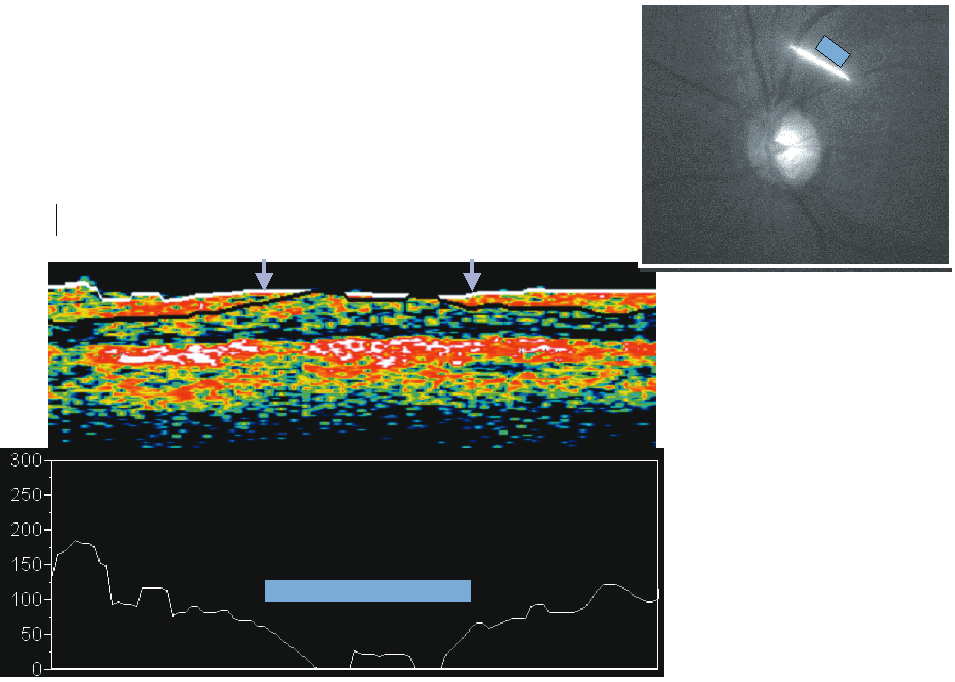

The pupil should be pharmacologically dilated during image acquisition to optimize optical alignment and avoid aberration caused by the pupillary edge. There is an internal and an external fixation target. The imaging lens is positioned 1 cm from eye to be examined and adjusted until the retina is in focus. An infrared-sensitive charge-coupled device (CCD) video camera displays the position of the scanning beam on retina. The first reflection measurement is the vitreoretinal interface that is demarcated by the contrast between the nonreflective vitreous and the high backscattering of the retinal surface. The highly reflective layer delineates the posterior boundary of the retina and corresponds to the retinal pigment epithelium. The inner margin of the retina shows another bright area of backscattering, a thin layer, that corresponds to the RNFL. Figure 17 is an example of a healthy eye in which the anterior and posterior highly reflecting layers can be seen (shown in red), representing the RNFL and retinal pigment epithelium, respectively. The inferotemporal and superotemporal nerve fiber bundles are evident as localized thickenings in both the RNFL and the retina. Figure 18 is an example of a glaucomatous eye with a broad focal defect in the superotemporal quadrant with thinning of the RNFL to less than 50 μm.

Fig. 17. Optical coherence tomography: healthy eye. In this example of a healthy eye, the anterior and posterior highly reflecting layers can be seen, representing the retinal nerve fiber layer (RNFL) and retinal pigment epithelium (RPE), respectively. The inferotemporal and superotemporal nerve fiber bundles are evident as localized thickenings in both the RNFL and the retina.

Fig. 18. Optical coherence tomography: glaucomatous eye. In this example of a glaucomatous eye, a broad focal defect in the superotemporal quadrant is seen with thinning of the retinal nerve fiber layer (RNFL) to less than 50 μm.